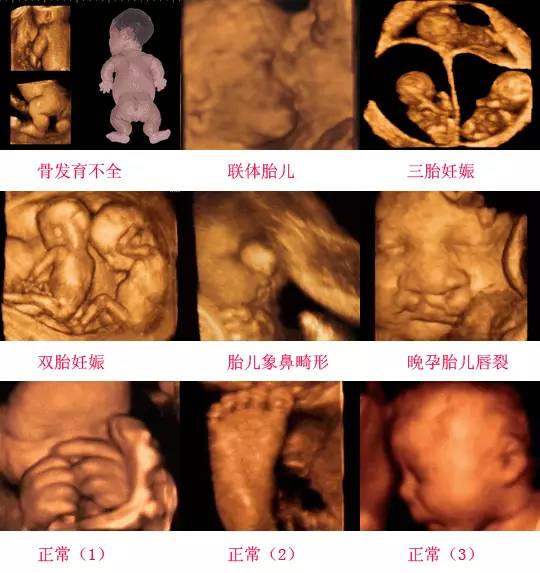

四維彩超是一種先進(jìn)的醫(yī)學(xué)影像技術(shù),通過實(shí)時(shí)觀察胎兒在母體內(nèi)的活動(dòng)情況,為醫(yī)生提供了豐富的診斷信息,在四維彩超下,我們可以清晰地觀察到胎兒的蛋蛋(睪丸)的形態(tài)、位置和大小等特征,胎兒蛋蛋是男性生殖系統(tǒng)的重要組成部分,對(duì)于胎兒的生長(zhǎng)發(fā)育具有重要意義。

在四維彩超下,胎兒蛋蛋呈現(xiàn)出特定的形態(tài)和外觀,通常情況下,胎兒蛋蛋呈現(xiàn)出圓形或橢圓形,表面光滑,內(nèi)部回聲均勻,隨著胎兒的發(fā)育,蛋蛋會(huì)逐漸增大,并呈現(xiàn)出明顯的性別特征,醫(yī)生可以通過四維彩超技術(shù),對(duì)胎兒蛋蛋的大小、形態(tài)和位置進(jìn)行評(píng)估,以判斷胎兒生殖系統(tǒng)的健康狀況。

四維彩超技術(shù)在評(píng)估胎兒蛋蛋發(fā)育方面具有重要意義,通過四維彩超,醫(yī)生可以實(shí)時(shí)觀察胎兒蛋蛋的形態(tài)、位置和大小等特征,了解胎兒生殖系統(tǒng)的發(fā)育情況,四維彩超還可以幫助醫(yī)生發(fā)現(xiàn)可能的異常情況,如睪丸未降、睪丸囊腫等,為及時(shí)采取治療措施提供依據(jù)。